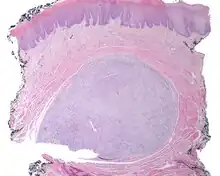

A very low power hematoxylin and eosin stained slide of an ectomesenchymal chondromyxoid tumor. Note the well demarcated tumor, separate from the overlying, intact squamous mucosa.

A very low power hematoxylin and eosin stained slide of an ectomesenchymal chondromyxoid tumor. Note the well demarcated tumor, separate from the overlying, intact squamous mucosa.

An intermediate power hematoxylin and eosin stained section of an ectomesenchymal chondromyxoid tumor, showing skeletal muscle entrapment. Note the "net-like" appearance (lower portion).[5][6] The overlying surface epithelium is intact and unconnected to the well circumscribed, but unencapsulated ectomesenchymal chondromyxoid tumor of the tongue. There are numerous skeletal muscle bundles at the periphery of the tumor.

The overlying surface epithelium is intact and unconnected to the well circumscribed, but unencapsulated ectomesenchymal chondromyxoid tumor of the tongue. There are numerous skeletal muscle bundles at the periphery of the tumor. - The tumor is made up of small round, oval, spindle, or stellate cells that have a very monotonous appearance. There are small dark nuclei with variably amounts of light to basophilic cytoplasm.[1][5][7]